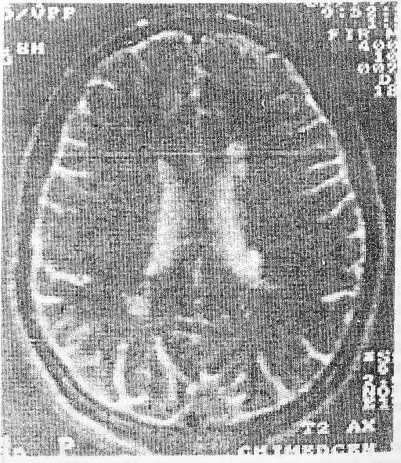

Оценка кровотока в интрацеребральных сосудах методами ТКДГ выявила в подавляющем числе случаев (18) различные степени его изменения — от незначительного снижения до затруднения перфузии. МР-томографическое исследование, проведенное всем больным, позволило подтвердить предполагаемый сосудистый характер поражения головного мозга, выявив изменения, характерные для цереброваскулярных заболеваний. Так, у всех больных диагностировано множественное очаговое поражение головного мозга с очагами округлой формы ишемического характера мелкого и среднего размера — 2—30 мм (рисунок). Очаги квалифицировались как инфарктные в случаях четкой демаркации их границ. Лейкоареозис предполагался в случаях их локализации исключительно в белом веществе полушарий, без распространения в кору, подкорковые ядра при отсутствии четкой демаркации, интактных, часто расширенных ипсилатеральных желудочках и прилегающих бороздах. Наиболее часто очаги располагались в перивентрикулярном и стриокапсулярном регионах, сочетаясь в отдельных случаях с корковыми. В последнем случае очаги имели большие размеры, часто сливной характер, переходя на белое вещество семиовального центра и наружной капсулы, обычно сочетаясь с мелкими, соответствующими по форме, величине и локализации лакунарными.

МРТ головного мозга больного С.Описание в тексте

У 3 больных с мозжечковыми нарушениями в клинической картине прослежено ее соответствие выявленным наряду с полушарными очагами мелкоочаговым поражениям мозжечка на МР-томограммах. У других же больных со статико-локомоторной атаксией не было обнаружено клинико-МРТ-соответствия, что, возможно, объясняется не поражением собственно мозжечка, а нарушением лобно-мозжечковых связей. У 2 больных с выраженными корковыми очагами на МР- томограмме не обнаружено корреляций между выраженностью неврологической симптома тики и степенью МРТ-верифицированных изменений в мозге. Так, ряд пациентов с множественными очагами, занявшими значительную часть полушарий, демонстрировали минимальный неврологический дефицит. В то же время больные с грубыми нарушениями ходьбы и дементивными расстройствами в ря де случаев имели негрубое поражение перивентрикулярного региона.